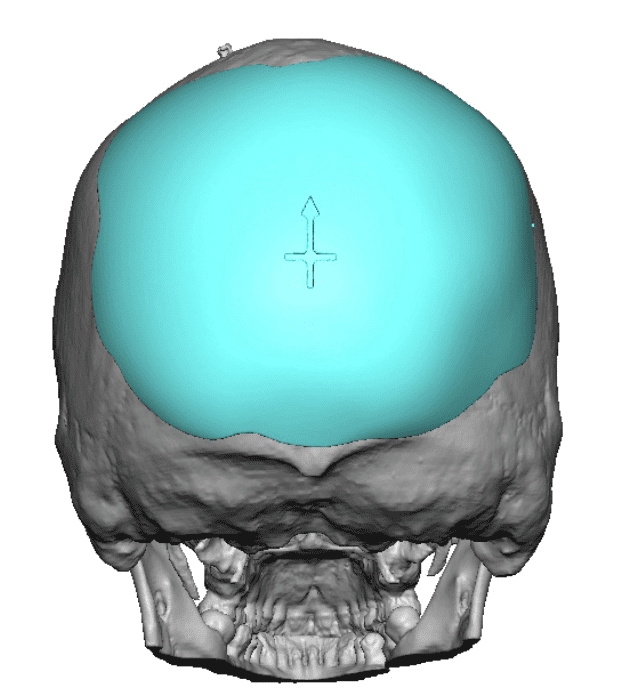

Desire for a higher and more prominent crown of the skull.

Crown of skull augmentation using a custom skull implant.

Desire for a higher and more prominent crown of the skull.

Crown of skull augmentation using a custom skull implant.